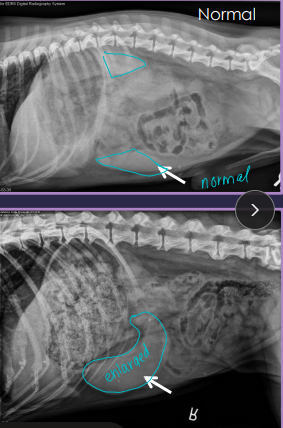

Splenic Torsion “acute abdomen”

Rads: abnormal location, mass effect, gas bubbles, comma-shaped spleen

US: variable echotexture, dilated vessels, thrombi